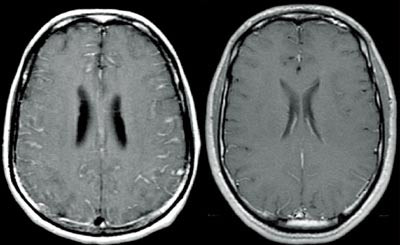

Differensialdiagnoser er cerebrale eller meningeale metastaser og kronisk meningoencefalitt av annen årsak, særlig tuberkuløs meningitt. Ved Hodgkins sykdom er intrakraniale metastaser sjeldent, mens kompliserende infeksjoner i sentralnervesystemet forekommer hyppigere. Neoplastisk meningitt ses derimot hyppig ved non-Hodgkins lymfom, særlig av aggressiv type (11). I spinalvæsken er det oftest moderat forhøyet antall leukocytter, forhøyet spinalproteinnivå og nedsatt glukosekonsentrasjon. CT og MR av hjernen kan gi varierende funn (fig 1). Det kan påvises ødem, pseudocyster og hydrocephalus (2).